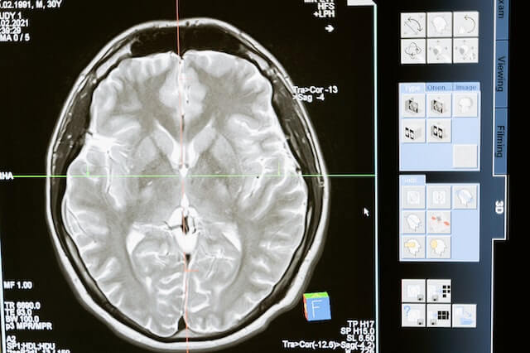

뇌졸증은 뇌혈관이 막히거나 터져서 뇌에 혈액 공급이 잘 되지 않아 생기는 질병으로, 세계적으로 사망률과 장애율이 높은 질병 중 하나입니다. 뇌졸증은 예방할 수 있고, 발생했을 때 적절한 대처법과 치료법을 알면 후유증을 줄일 수 있습니다. 이 글에서는 뇌졸증의 원인, 예방, 대처법, 치료법에 대해 간단하게 알아보겠습니다.